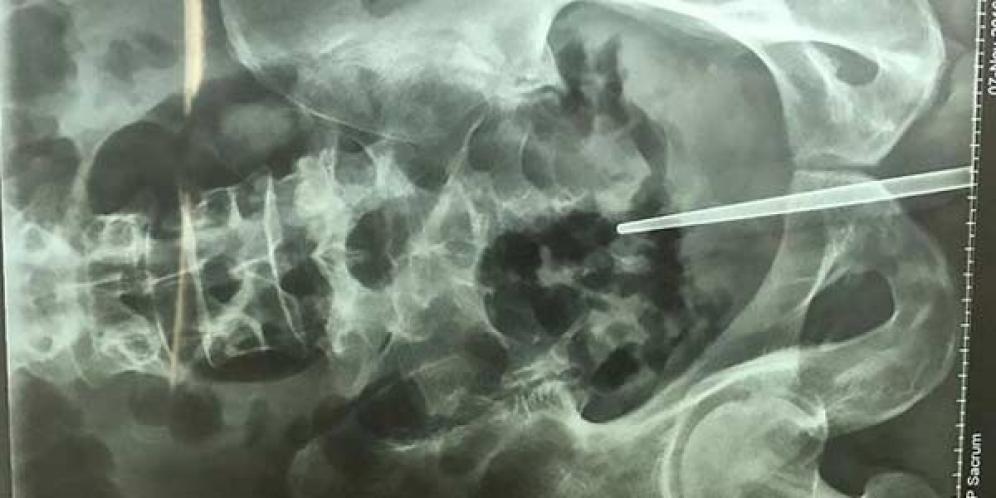

Dokter Temukan Sumpit Dalam Penis Pria di China

Sebuah rumah sakit di China mendapatkan kasus yang sangat tak biasa dan mengejutkan dari kondisi fisik pasiennya. Pasalnya, setelah menjalani serangkaian pemeriksaan...

Ngeseks dengan Botol, Penis Pria Ini Akhirnya Diamputasi

Beritabali.com, Tegucigalpa. Seorang pria di Honduras harus rela kehilangan penisnya setelah dokter terpaksa mengamputasi organ vitalnya itu demi menyelamatkan ny...